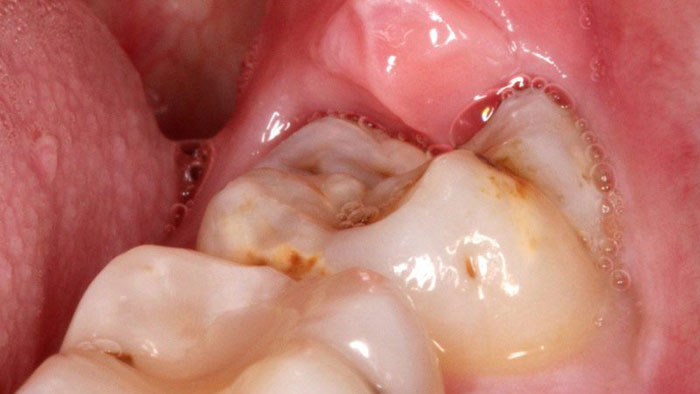

The gum overlying the tooth may get infected causing severe pain and discomfort radiating to the jaws, ear, temple region. The wisdom teeth, if they erupt in an abnormal position cause changes in the temporomandibular joint leading to problems over a period of time and also can damage to the adjacent teeth. The abnormal position of the teeth may cause difficulty in brushing and maintaining good hygiene of the teeth.

Here in SACHIN DENTAL CLINIC, the whole procedure is done in a highly sterilized environment. Prior to the removal, an X-Ray evaluation and the possible complications are discussed with the patient.